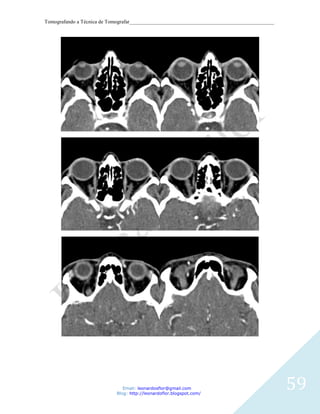

Imagem 1

Corte axial. 1, Cavidade orbitária. 2, Seio frontal. 3, Osso esfenóide

Imagem 2 - Corte axial. 1, Globo ocular. 2, Septo nasal. 3, Células etmoidais. 4, Seios

esfenóidal. 5, Hipófise. 6, Dorso sellae.

Imagem 3

Corte axial. 1, Globo ocular. 2, Septo nasal. 3, Células etmoidais. 4, Seios esfenóidal. 5,

Clivus.

Imagem 4

Corte axial. 1, Seio maxilar esquerdo. 2, Canal nasolacrimal. 3, Concha. 4, Septo nasal. 5,

Arco zigomático. 6, Processo condilar da mandíbula.

Imagem 5

Corte axial. 1, Concha. 2, Seio maxilar. 3, Asa lateral do processo pterigóideo. 4,

Nasofaringe. 5, Atlas (C1). 6, Fenda do palato ptérigo.

Imagem 6

Corte axial. 1, Seio maxilar. 2, Apófisis pterigoides,. 3, Nasofaringe. 4, Mandíbula. 5, Arco

45

anterior do atlas. 6, dente do áxis (Processo odontoide).